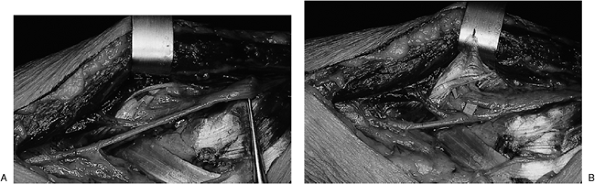

Figure 7.3-2 Fresh cadaver dissection of the ECRB and supinator. (A) The fibrous tissue edges of the ECRB and the supinator are in close proximity to the PIN as it enters the supinator. (B)

The ECRB has been reflected superiorly. Fat has been removed from around the supinator to reveal its two heads and to reveal the fibrous tissue edge of the superficial head that forms the arcade of Frohse. |